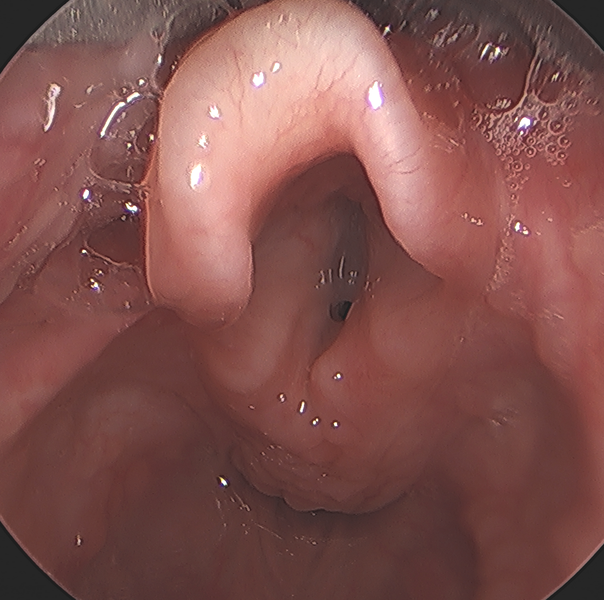

Laryngomalacia